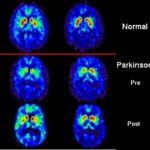

Immagine: Public Domain